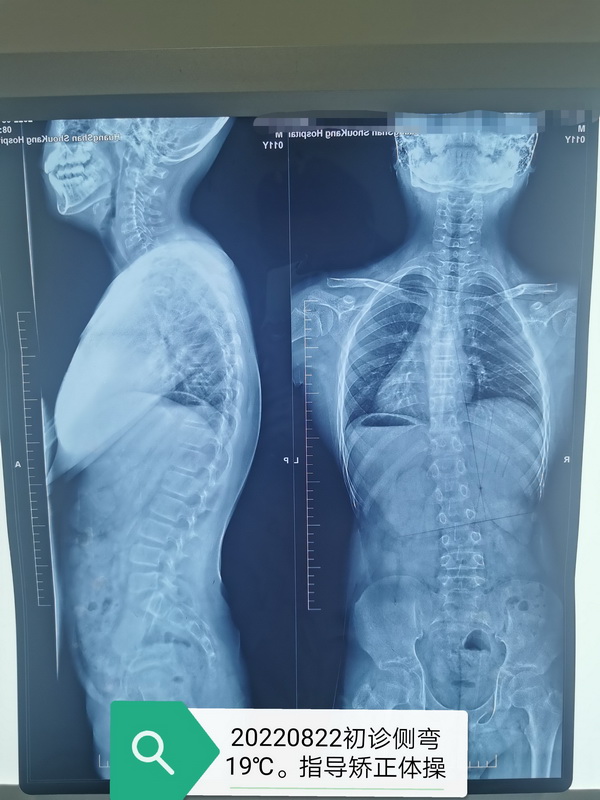

何庚午副主任为小林定制了个性化治疗方案。根据小林的侧弯类型、位置、度数,何庚午副主任为其定制侧弯支具,还指导她做矫正训练动作,一遍遍地纠正,一次次地演示,同时还教会小林保持良好的站姿、坐姿、睡姿,选择合适的枕头和床垫。

在康复运动医学科,有很多像小林一样每日坚持做矫正训练动作的孩子们,经过长期锻炼,孩子们在脊柱侧弯矫正与体态改善方面均取得显著的成果,让我们一起来看看效果吧!

矫正前VS 矫正后 矫正前VS矫正后 矫正前 VS矫正后